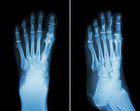

(图:申先生治疗后的脚部X光)

第一个疗程治疗后,申先生的双足关节刺痛感减轻,晨起僵硬有所缓解,夜间发作次数也减少了。

第二个疗程治疗后,申先生的双足第一跖趾关节痛风石溶解不少,按压无疼痛,夜间不再发作。陈建春主任又为其安排了一个疗程的辅助治疗,采用无针介入术,控制关节炎症发展,阻止骨质继续受损,修复受损软骨组织改善活动能力的治疗效果与康复巩固目的。

第三个疗程治疗后,申先生的双足第一跖趾关节痛风石已全部溶解,关节活动恢复正常状态。复查也显示各项指标均一切正常,已达临床康复标准。离院前,陈建春主任嘱咐申先生,回去后要合理饮食,多饮水,多食水果蔬菜,适当锻炼身体,不可熬夜。